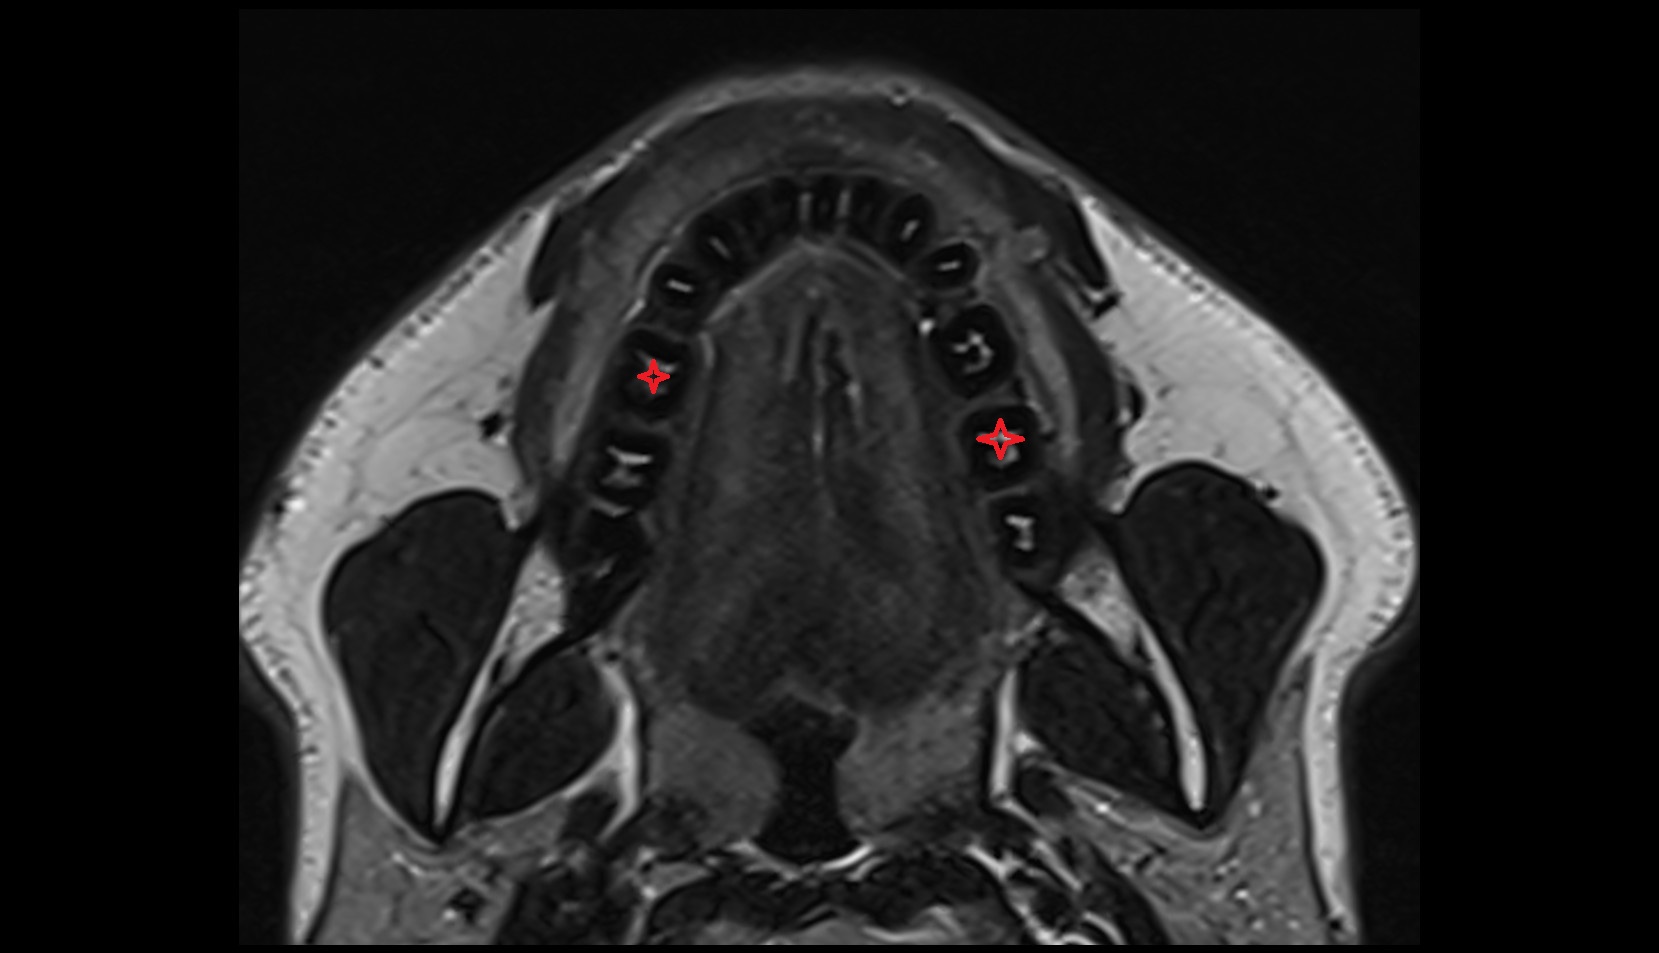

- Temporomandibular joint

- Mandibular condyle

- Mandibular fossa

- Superior head of lateral pterygoid muscle

- Inferior head of lateral pterygoid muscle

- Lateral pterygoid muscle

- Masseter muscle

- Medial pterygoid muscle

- Temporalis muscle